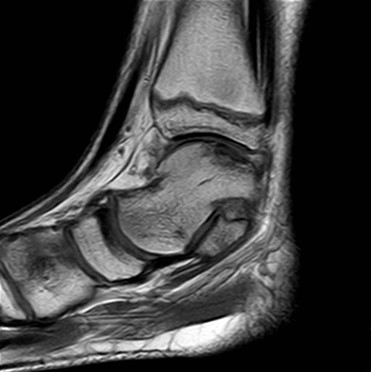

MRT

Die Kernspintomographie hat ihre Stärke in der Darstellung von Weichteilverletzungen. Insbesondere Verletzungen der Wachstumsfuge, des Periosts und der Bänder lassen sich gut visualisieren. Nachteilig ist die Untersuchungsdauer von 20-30 Minuten. Bleibt das Kind während dieser Zeit nicht ruhig liegen, kommt es zu Bewegungsartefakten, welche die Beurteilbarkeit der Bilder beeinträchtigen.

Os trigonum

Das Os trigonum lässt sich als isolierter Knochen dorsal des Talus seitlichen Röntgenbild darstellen. Normalerweise hat das Os trigonum keine klinische Relevanz. Bei entsprechenden Beschwerden und einer Aktivierung im MRT kann der Knochen arthroskopisch entfernt werden. Gehäuft beobachten wir eine mechanische Problematik durch das Os trigonum bei jugendlichen Fußballspielern und Tänzerinnen.